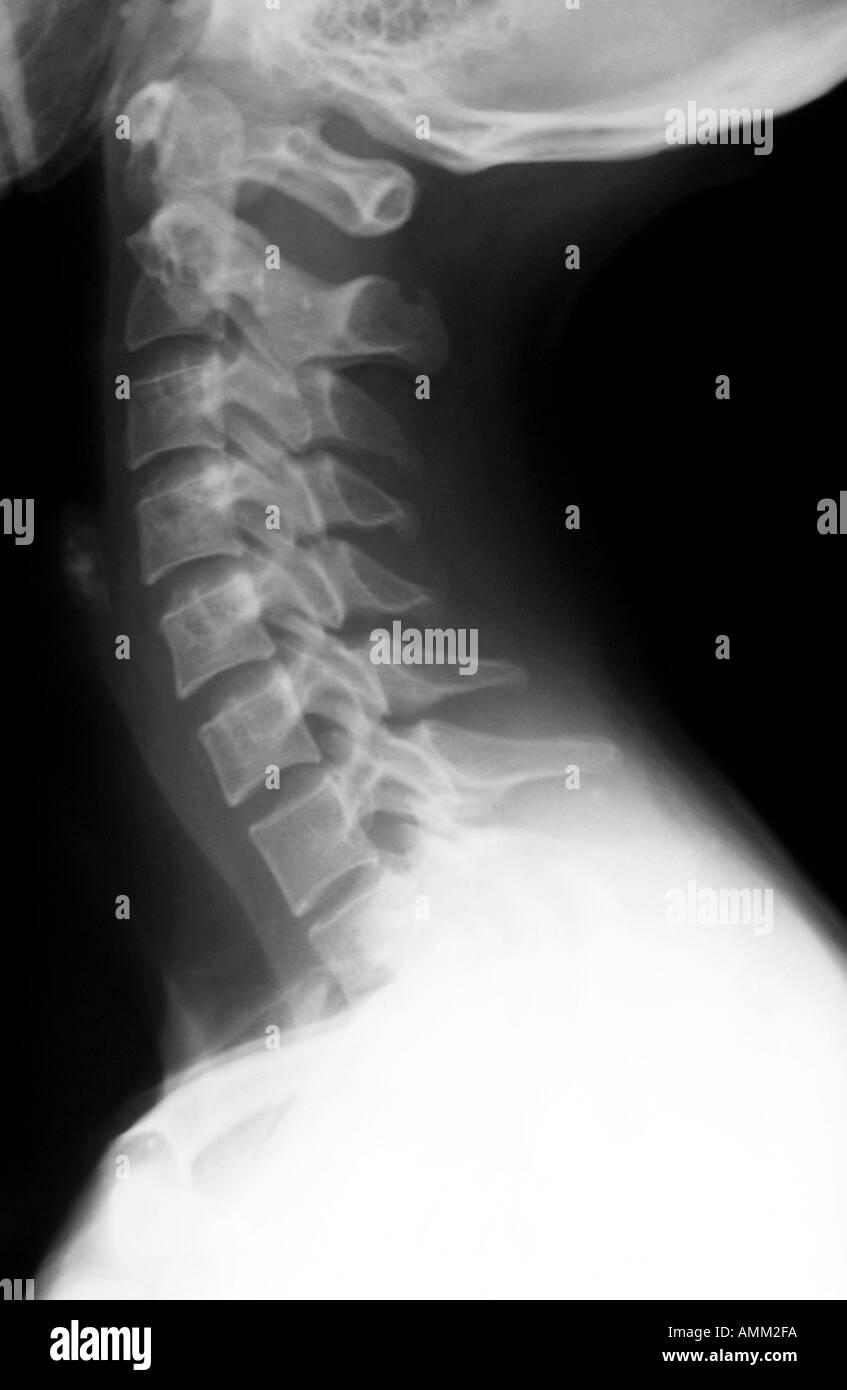

Descubre más de 109 búsqueda relacionada, búsqueda caliente, palabras clave de. Suele ser una zona donde se acumula la tensión provocada por las malas posturas, el desgaste o la ansiedad.esto puede derivar en diversos problemas entre los cuales, inevitablemente, están los temibles mareos. Il répond habituellement bien aux. A medida que maduran, las células escamosas normales se desplazan desde las capas más profundas de la cérvix. La radiografía de la columna cervical es un estudio seguro e indoloro en el que se utiliza una pequeña cantidad de radiación para obtener una imagen de los huesos de la parte posterior del cuello (vértebras cervicales).

Aquí se describen las características generales de la tercera a la sexta vértebras cervicales. Descubre más de 109 búsqueda relacionada, búsqueda caliente, palabras clave de. Hémostase à la pince bipolaire. Las vértebras del tronco (divididas en vértebras torácicas y lumbares en los mamíferos ) se encuentran caudales (hacia la cola) de las vértebras cervicales. Las células cervicales, incluso las normales, experimentan cambios de manera constante. Anatomía de la columna cervical (cuello) la columna cervical comienza en la base del cráneo. Cada vértebra cervical se denomina c1, c2, c3, c4, c5, c6 y c7. Variantes anatómicas de la columna vertebral priscila martínez gónzalez.

Examples have not been reviewed. Aquí se describen las características generales de la tercera a la sexta vértebras cervicales. Video celulas cervicales normales y anormalesvisita: «optrascan está redefiniendo la detección de cáncer de cuello uterino al introducir cytosia, que ofrece una gran variedad de características para analizar eficazmente las láminas de citología con base líquida y las citologías cervicales a fin de diferenciar entre las células cervicales normales y anormales utilizando las clasificaciones de bethesda sobre carcinoma de células. Purpose the aim of the study is to analyze the efficacy of the osteopathic treatment on whiplash diagnosed patients. Las adenopatías cervicales son las adenopatías localizadas más frecuentes. « optrascan redéfinit le dépistage du cancer du col de l'utérus en introduisant cytosia, qui offre une pléthore de fonctions permettant d'examiner efficacement les lames de cytologie en. Las células cervicales, incluso las normales, experimentan cambios de manera constante. Los mareos cervicales pueden deberse a contracturas o a lesiones permanentes de más o menos gravedad y, aunque no llegan a ser tan incapacitantes como el vértigo, pueden obligar a tomar unos días de baja. Con el tiempo, estas células se vuelven planas y cubren la superficie de la cérvix. La primera, segunda y séptima vértebras son extraordinarias y se detallan más adelante. A medida que maduran, las células escamosas normales se desplazan desde las capas más profundas de la cérvix. 2 placas de toda la columna vertebral, en impactos de frente y de perfil, permiten numerar las vértebras de la columna y muestran las curvaturas fisiológicas (lordosis cervical, cifosis torácica, lordosis lumbar, cifosis sacra).